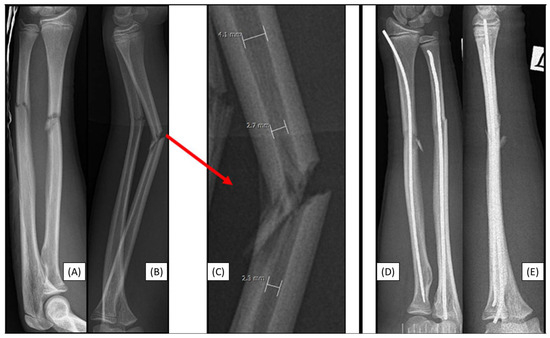

3.2. Case 2: Narrow Medullary Cavity